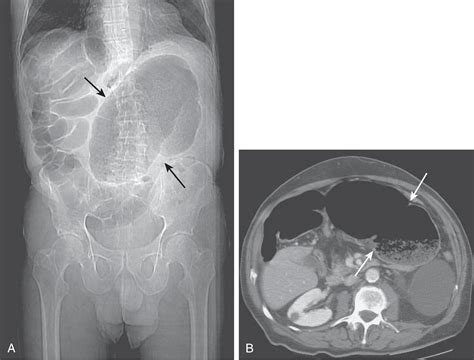

• Radiographic Imaging: It is frequently used in chest X-rays to detect small amounts of pleural effusion or pneumothorax that might not be visible in an upright or supine position.

• Abdominal Imaging: It helps in shifting bowel loops, which can obscure the visualization of the gallbladder, kidneys, or other retroperitoneal structures.

When performing imaging in the Right Lateral Decubitus position, technicians must be precise with beam angulation and patient orientation. If the goal is to detect a pleural effusion, the patient is placed so that the side being examined is the "down" side. This allows the fluid to gravitate to the dependent portion of the thoracic cavity, where it is more easily identified against the chest wall. Conversely, if searching for free intraperitoneal air (pneumoperitoneum), the patient is often placed so that the potential air space is at the highest point.

Proper documentation is equally important. Radiographic films or digital images must be clearly marked as "Right Lateral Decubitus" to ensure that the interpreting radiologist understands the orientation of the anatomy. Failure to label correctly can lead to diagnostic errors, especially when distinguishing between various types of opacities or lucencies on a scan.